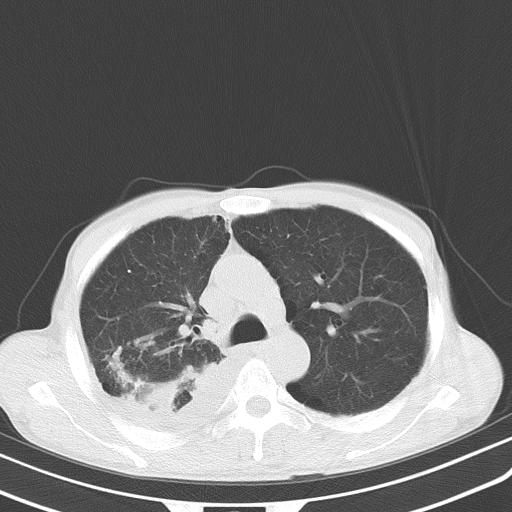

男性 75  咳嗽 一周前发热最高达39

右肺继发型tb并右侧tb性胸腔炎,右侧胸腔大量积液并右下肺膨胀不全,慢支肺气肿、多发肺大泡。建议抽胸水实验室检查并复查排除恶性在占位。

右上肺继发型肺结核,右胸腔中等量积液。

左上肺大泡。

结核的基础上有纵隔淋巴结肿大,右侧有胸水,但右侧纵隔反而窄,说明有肺有不张。

再就是右下肺有块影,和不张混合,还是不能除外肺癌。

补充材料,患者2月份ct片大致正常,双侧胸腔积液,2月份抽胸水未发现ca细胞,现患者发热,痰多,各气管通畅,

1)右肺继发型肺结核。2)左肺胸膜下多发性肺大泡。3)右侧胸腔积液。